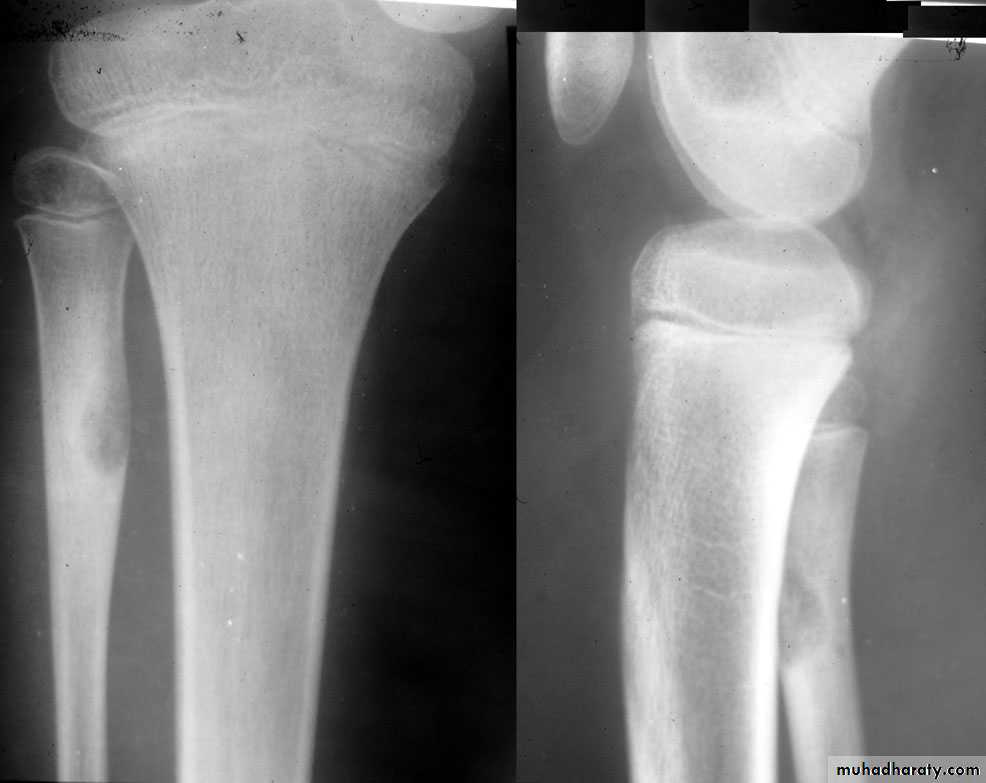

Benign bone tumoursFibrous cortical defect

= non-ossifying fibromaVery common

ChildAccidentally on XR

Pain or pathologic fractureNo malignant potential

Rx : curettage + bone graftOsteoid osteoma